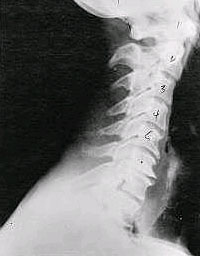

| Phase Three Subluxation Degeneration

Phase Three has all the attributes of the previous phases, but they are more distinct. The curvature is abnormal, and the disc spaces are dramatically decreased and changed. The calcium projections on the spine are abundant. People in Phase Three suffer from a restricted range of motion and, upon presentation, are clearly exhibiting symptoms. |

Phase Four Subluxation Degeneration

Phase Four is a grave condition that affects the patient's longevity and quality of life. Note that the X-rays of this Phase Four patient show not only massive calcium projections, but severe structural damage as well. The bones themselves even seem fused. People with Phase Four Subluxation Degeneration not only experience a severe restriction in their range of motion, but probably suffer from a number of other health issued due to the neurological damage caused by years of untreated subluxation. |